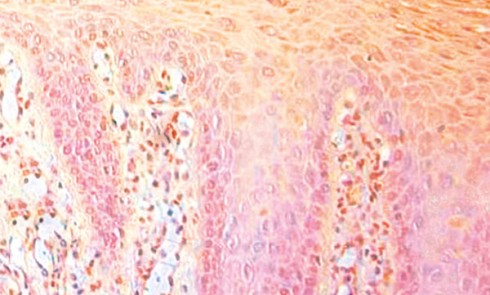

Article réservé à nos abonnés La muqueuse buccale et ses altérations physiopathologiques

Chaque lésion élémentaire représente une altération clé sur le plan histologique qui donne des indices quant à l’origine de cette...